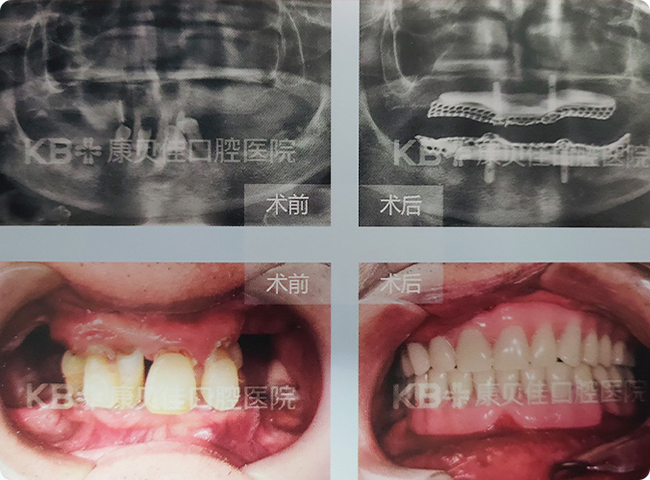

周先生 82岁

多颗牙缺失,伴有下颌囊肿,因为种植难度太大,很多医生都不愿意接手。到院后经CT明确囊肿部位与大小后,康贝佳口腔种植专家帮其成功摘除囊肿后,采用常规技术帮其种牙,恢复咀嚼功能,提高生活品质。

治疗方案:

下颌种植4颗恢复半口